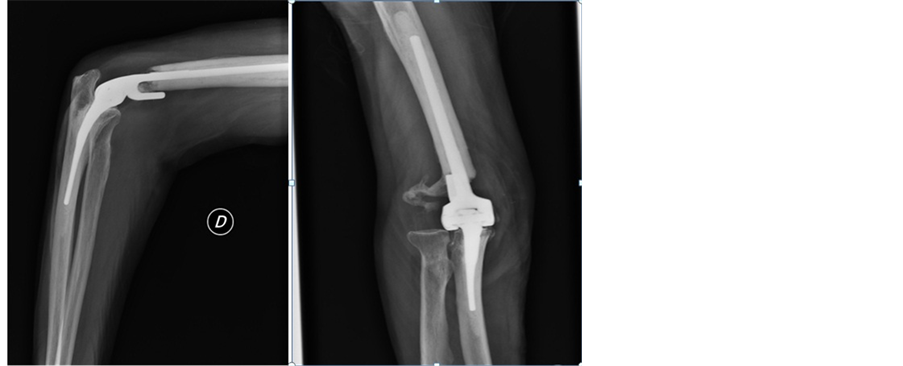

Our patient underwent total elbow prosthesis (Figure 3): the surgical approach was later centered on the olecranon, neurolysis of the ulnar nerve, para-internal and external passing triceps.

Figure 3. Image showing the X-ray control of the elbow prosthesis.

An intraoperative biopsy objectified an evocative bone metastasis of a clear cell carcinoma of renal cells. The postoperative course was simple, with almost complete recovery of range of motion.